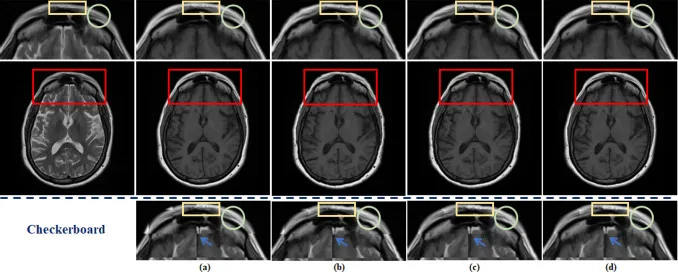

图10. 空间配准在fastMRI数据集上的效果可视化。(a)显示了原始全采样T1图像。(b)表示通过传统方法将欠采样T2图像与全采样T1图像对齐的结果。©描绘了将传统空间配准与重建集成进行联合优化的结果。(d)显示了DUN-SA的结果。细节显示在第一行:对齐T1图像的放大视图,以及第三行:棋盘格可视化图的放大视图。